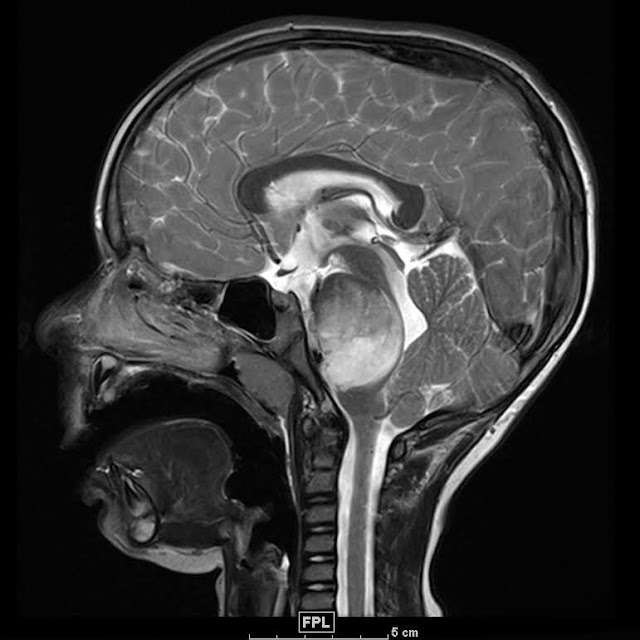

«Κατά τη διάρκεια μιας σειράς μαγνητικών τομογραφιών, είδα τον όγκο να εξαφανίζεται εντελώς», δήλωσε ο Γκριλ στο AFP.

Το DIPG, ή διάχυτο εγγενές γλοιώδες πόντιο , είναι ένας τύπος όγκου εγκεφάλου που εντοπίζεται σε μια περιοχή του εγκεφαλικού στελέχους γνωστή ως γέφυρα. Το όνομα διάχυτο εγγενές γλοιώδες ποντιακό περιγράφει πώς αναπτύσσεται ο όγκος, πού εντοπίζεται και ποια είδη κυττάρων προκαλούν τον όγκο.

Το Pontine δείχνει ότι ο όγκος βρίσκεται σε ένα τμήμα του εγκεφαλικού στελέχους που ονομάζεται γέφυρα . Η γέφυρα είναι υπεύθυνη για μια σειρά από σημαντικές σωματικές λειτουργίες, όπως η αναπνοή, ο ύπνος, ο έλεγχος της ουροδόχου κύστης και η ισορροπία.

Το γλοίωμα είναι ένας γενικός όρος για όγκους που προέρχονται από νευρογλοιακά κύτταρα. Τα νευρογλοιακά κύτταρα βρίσκονται σε όλο τον εγκέφαλο. Αποτελούν τη λευκή ουσία του εγκεφάλου που περιβάλλει και υποστηρίζει τους νευρώνες (οι νευρώνες είναι κύτταρα που μεταφέρουν μηνύματα στον εγκέφαλο).